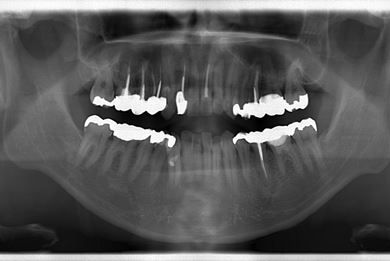

性別/年齢 男性 / 37歳

主訴 白い詰め物の修復などのメンテナンスを希望。

治療方針 セラミック治療にて、審美的回復を行う。

治療内容 オールセラミッククラウン1本(オールセラミック用土台1本)

総治療費 143,325円

治療期間 2ヶ月